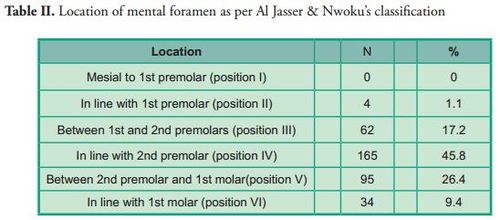

The most frequent location of the mental foramen was the longitudinal axis of the second premolar on both sides (position IV), followed by positions V, III, VI and II. No mental foramen was found in position I, neither significant differences compared to the contralateral side (p*0.764) (Table II).

The most frequent location of the mental foramen was the longitudinal axis of the second premolar on both sides (position IV), followed by positions V, III, VI and II. No mental foramen was found in position I, neither significant differences compared to the contralateral side (p*0.764) (Table II).

3D reconstruction was used to determine the location, shape and presence of accessory holes. To determine the location, the longitudinal axes of teeth were taken as reference as per Al Jasser & Nwoku's classification (21). Position 1: Mesial to first premolar; position 2: In line with first premolar; position 3: Between first and second premolars; position 4: In line with second premolar; position 5: Between second premolar and first molar, position 6: In line with first molar (Figure 3).

3D reconstruction was used to determine the location, shape and presence of accessory holes. To determine the location, the longitudinal axes of teeth were taken as reference as per Al Jasser & Nwoku's classification (21). Position 1: Mesial to first premolar; position 2: In line with first premolar; position 3: Between first and second premolars; position 4: In line with second premolar; position 5: Between second premolar and first molar, position 6: In line with first molar (Figure 3).

There is considerable debate in the literature regarding the location of the mental foramen in different ethnic groups. This study showed that this structure was found in all the samples between the root of the first premolar and the root of the first molar.

These results are similar to those of other studies (4, 6, 11, 13–17, 24), where the mental foramen was found on the longitudinal axis of the second premolar (Position IV). Other studies (7, 12, 18, 19) showed that the most frequent location of the mental foramen was position III, which differs from this study, as positions V and III ranked second and third respectively regarding frequency.

These results are similar to those of other studies (4, 6, 11, 13–17, 24), where the mental foramen was found on the longitudinal axis of the second premolar (Position IV). Other studies (7, 12, 18, 19) showed that the most frequent location of the mental foramen was position III, which differs from this study, as positions V and III ranked second and third respectively regarding frequency.